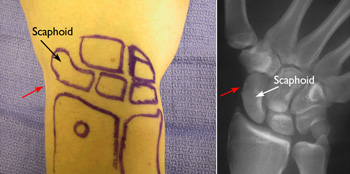

The scaphoid bone can most easily be identified when your thumb is held in a "hitch-hiking" position. It is located at the base of the hollow made by the thumb tendons. Often referred to as the "anatomic snuffbox," this area is typically the site of tenderness or pain when a fracture occurs.

Photograph and x-ray showing the location of the scaphoid in the wrist. The red arrows indicate the location of the anatomic snuffbox.